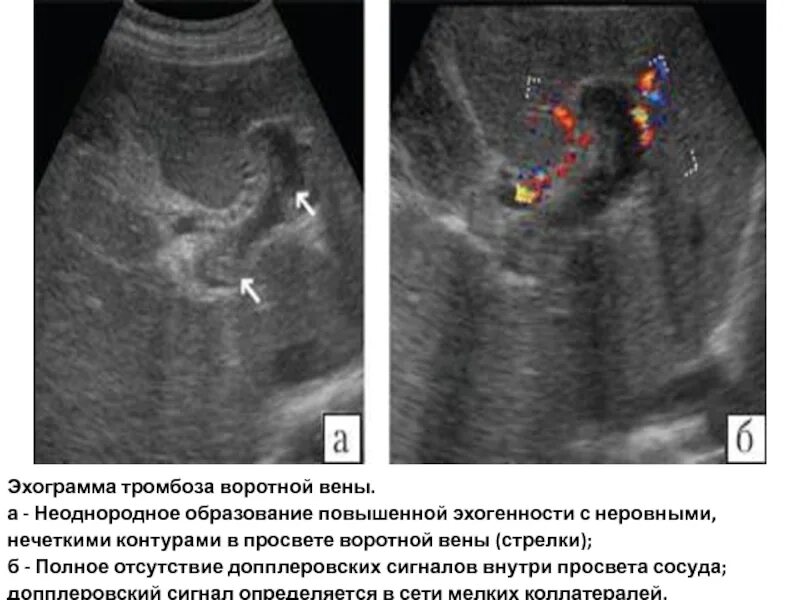

Повышенной эхогенности неоднородной структуры